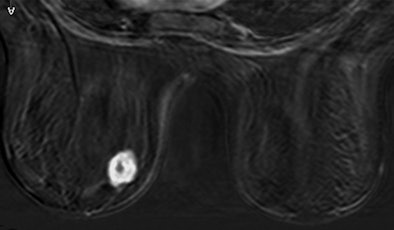

| Above, subtracted contrast-enhanced T1-weighted axial MR image shows focal area of intense F-18 FDG uptake and marked gadolinium enhancement in inferior inner quadrant of left breast. |